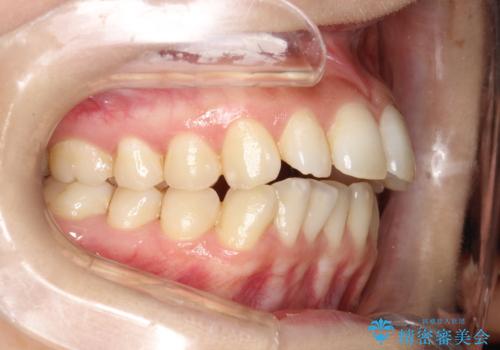

30代男性 インビザラインによる過蓋咬合の改善

- インビザラインG5のシステムにより過蓋咬合の改善をはかります。

ワイヤー治療では非常に困難な、著しい前歯の傾斜を伴う過蓋咬合ですが、マウスピースにより割と短期間で状態を改善することができます。